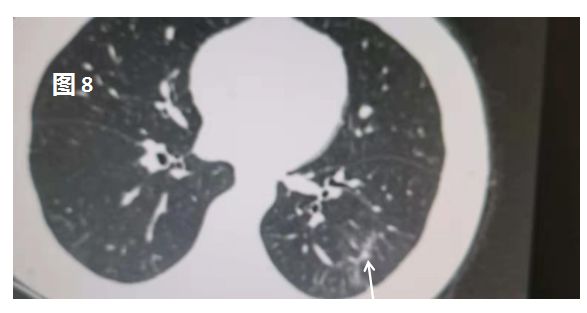

随着病情发展,实变区域开始吸收,密度减低,逐渐成为磨玻璃密度影,就像一颗糖 融化了,有效的治疗或机体的免疫力可以逐步战胜病毒,炎症会进一步吸收,范围逐步缩小,或许会留下纤维条索灶。这对于患者而言,可能真的就和得了一场流感差不多。比如图8